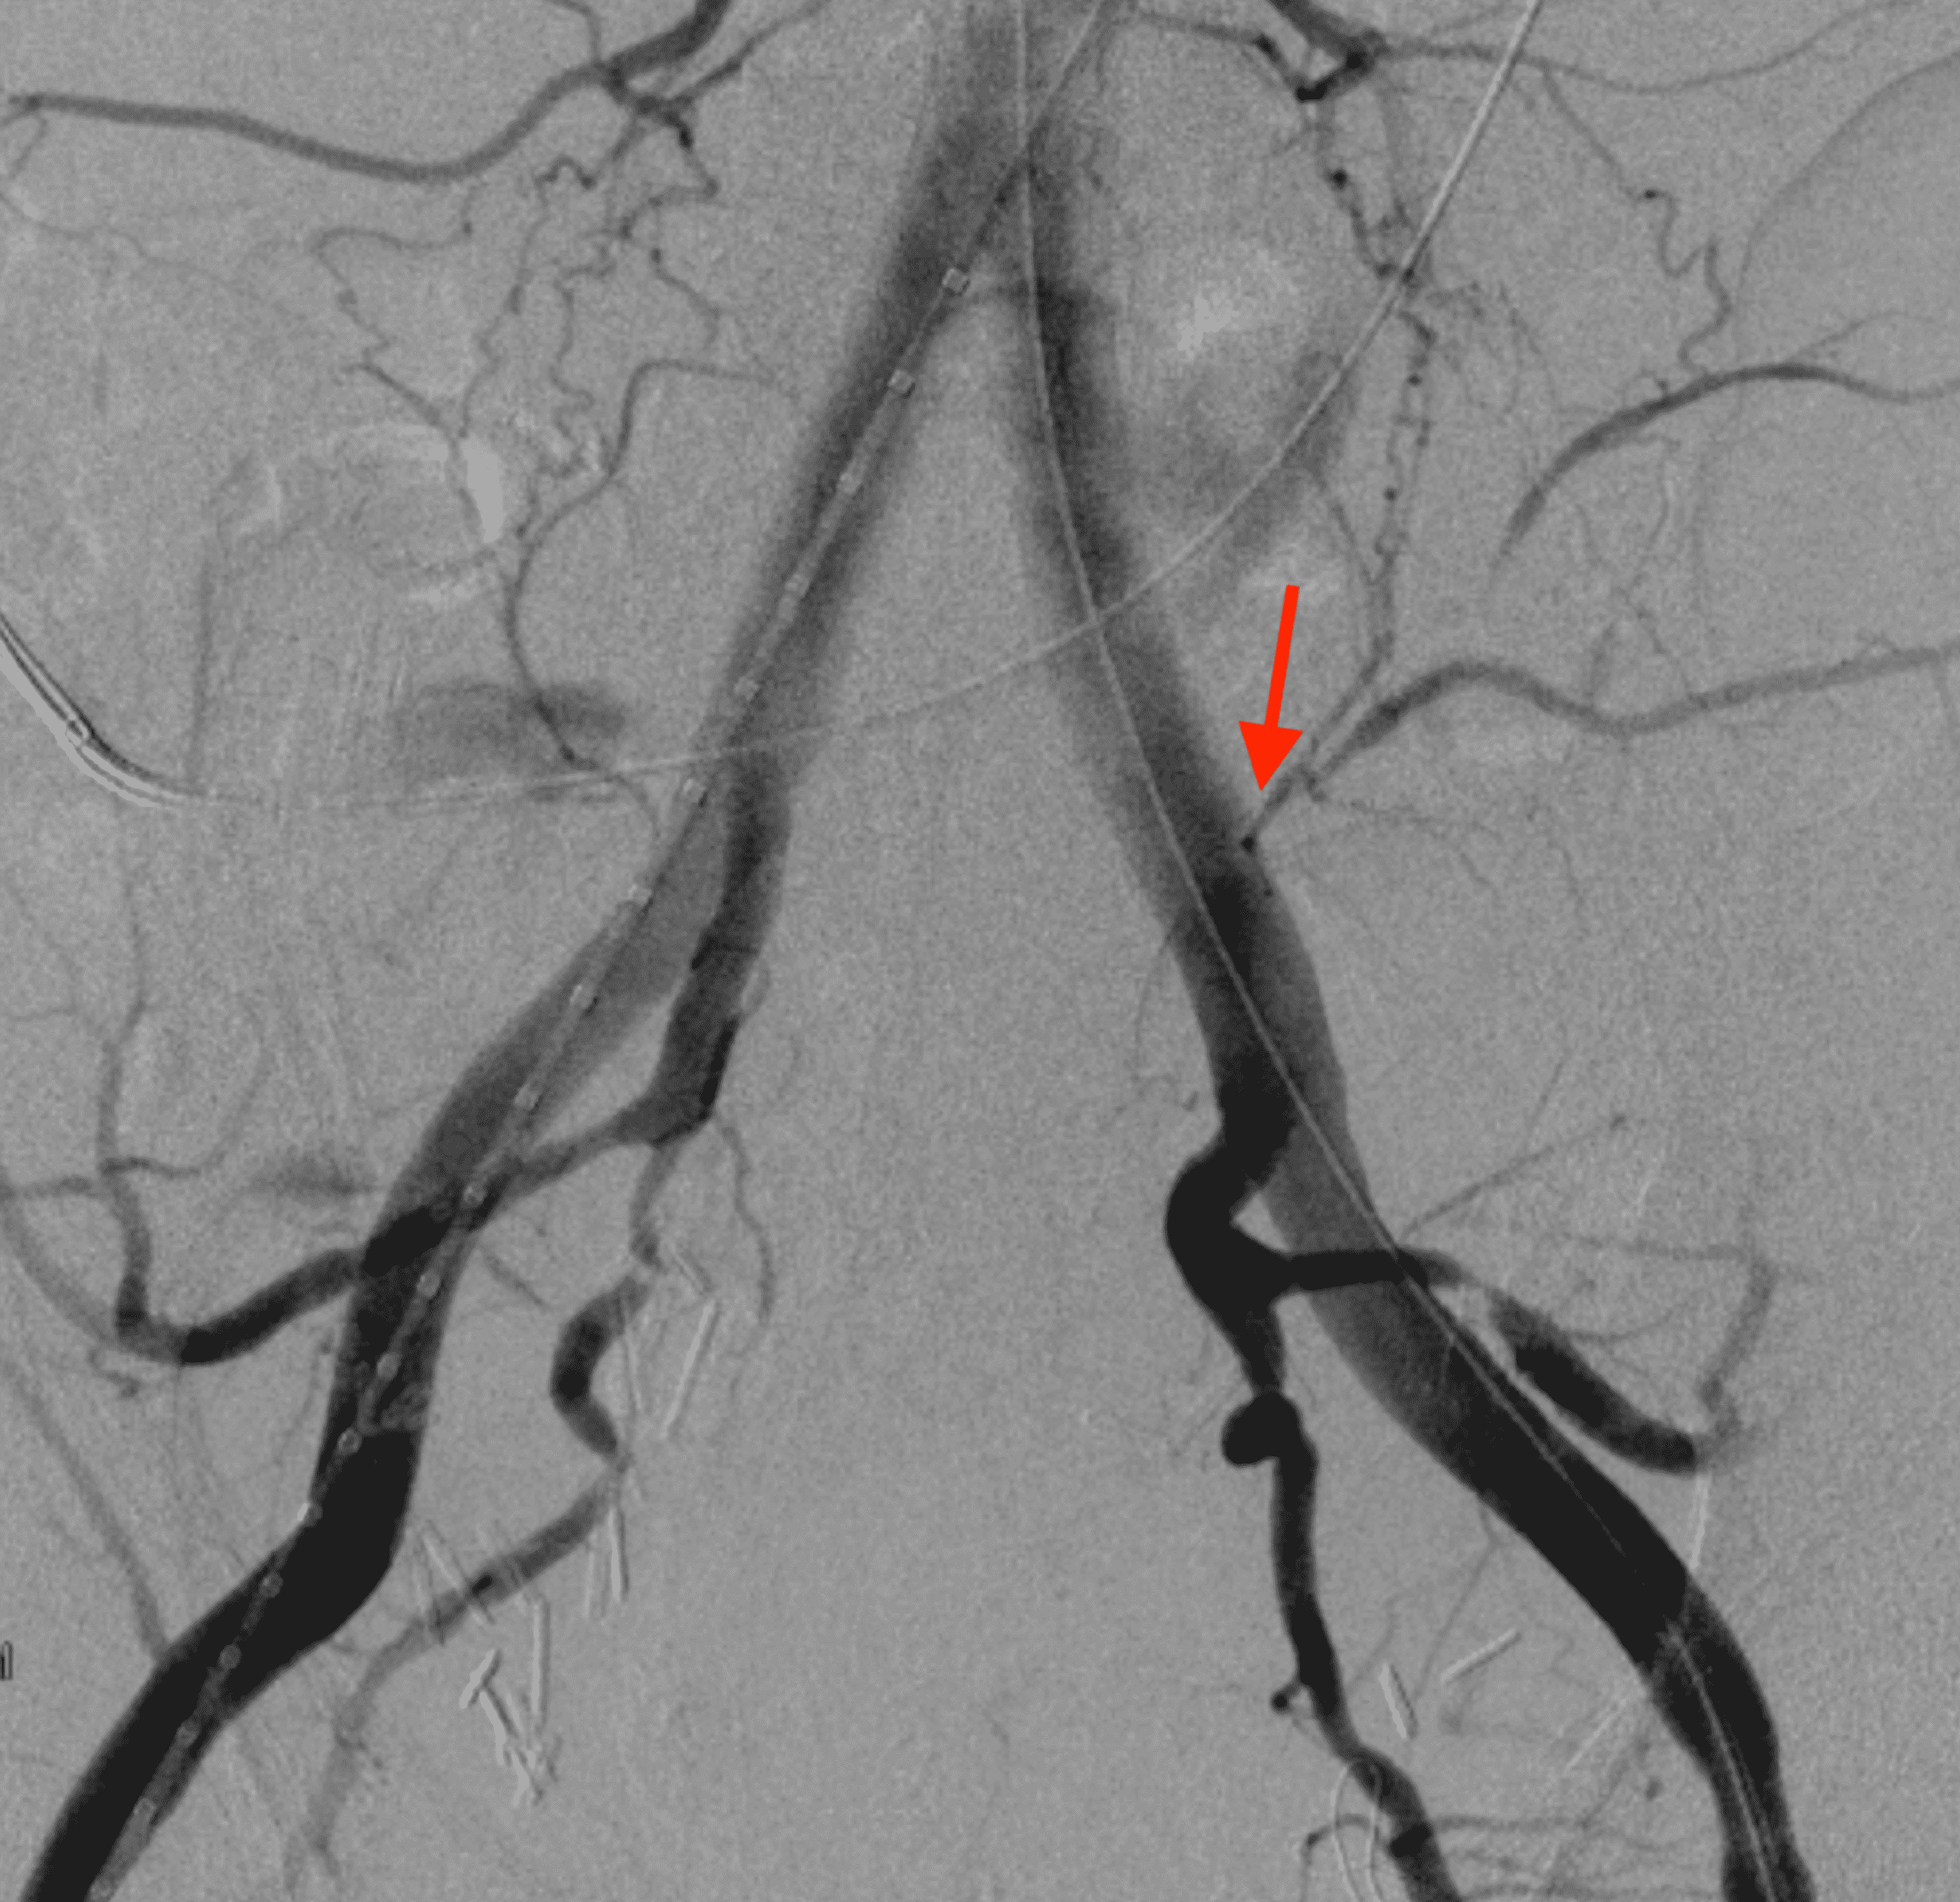

Arterioureteral Fistula in the Setting of Radical Cystoprostatectomy

Fistula formation between the external iliac artery and ileal conduit What Is A Cystoprostatectomy With Ileal Conduit It means that the tumours have grown through the lining of the bladder into or through the bladder muscle. It involves using a section of your small intestine (ileum) to create a conduit for urine. During your surgery, your doctor will remove your. It uses about 15 centimeters of the small. An ileal conduit is also known as a urinary. What Is A Cystoprostatectomy With Ileal Conduit.

Arterioureteral Fistula in the Setting of Radical Cystoprostatectomy What Is A Cystoprostatectomy With Ileal Conduit It means that the tumours have grown through the lining of the bladder into or through the bladder muscle. An ileal conduit will be the new storage area for your. It involves using a section of your small intestine (ileum) to create a conduit for urine. It uses about 15 centimeters of the small. One end of your intestine is. What Is A Cystoprostatectomy With Ileal Conduit.

Cureus Arterioureteral Fistula in the Setting of Radical What Is A Cystoprostatectomy With Ileal Conduit An ileal conduit will be the new storage area for your. What is an ileal conduit? The most commonly performed urinary diversion is an incontinent diversion, the ileal conduit. One end of your intestine is connected to your ureters, and the other end forms a stoma (a. During your surgery, your doctor will remove your. This is the simplest type. What Is A Cystoprostatectomy With Ileal Conduit.